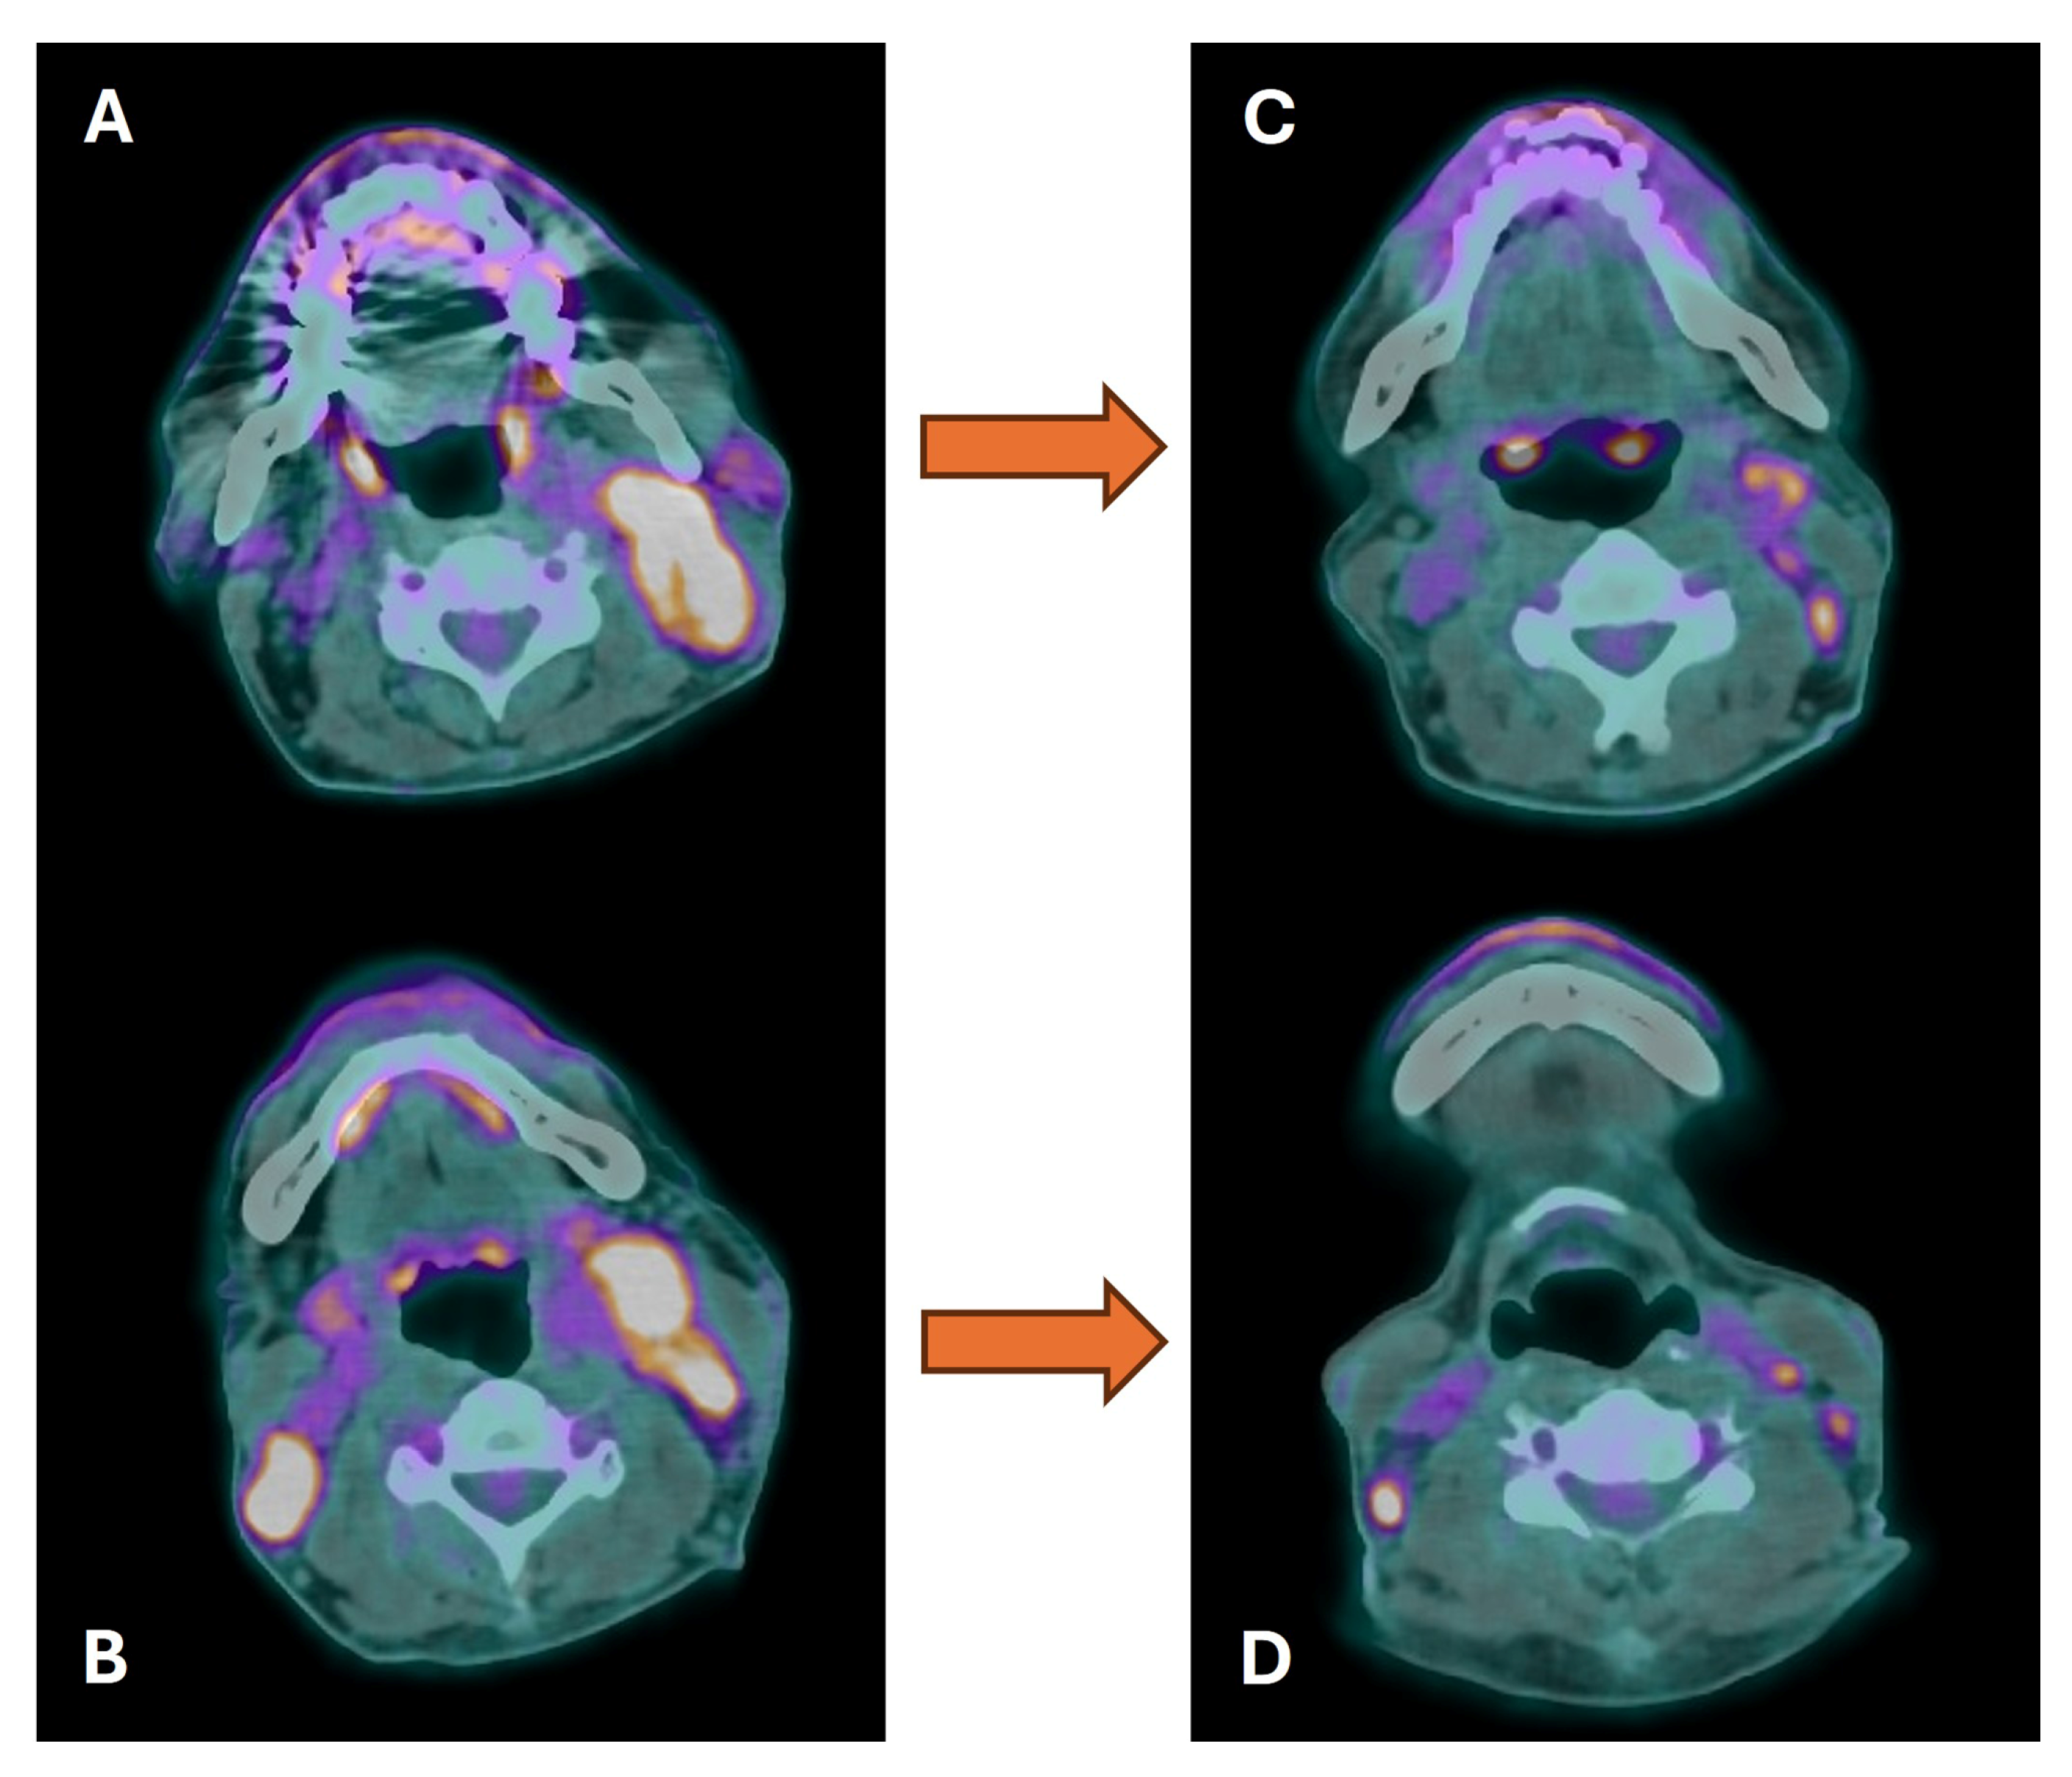

- van den Bosch, S.; Vogel, W.V.; Raaijmakers, C.P.; Dijkema, T.; Terhaard, C.H.J.; Al-Mamgani, A.; Kaanders, J.H.A.M. Implications of improved diagnostic imaging of small nodal metastases in head and neck cancer: Radiotherapy target volume transformation and dose de-escalation. Radiother. Oncol. 2018, 128, 472–478. [Google Scholar] [CrossRef]

- van den Bosch, S.; Dijkema, T.; Kunze-Busch, M.C.; Terhaard, C.H.; Raaijmakers, C.P.; Doornaert, P.A.; Hoebers, F.J.; Vergeer, M.R.; Kreike, B.; Wijers, O.B.; et al. Uniform FDG-PET guided GRAdient Dose prEscription to reduce late Radiation Toxicity (UPGRADE-RT): Study protocol for a randomized clinical trial with dose reduction to the elective neck in head and neck squamous cell carcinoma. BMC Cancer 2017, 17, 208. [Google Scholar] [CrossRef]